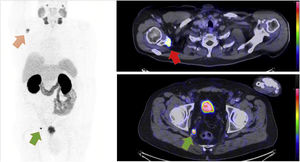

72-year-old male with prostate cancer cT3b, Gleason 7b and PSA level of 23 µg/l. Two weeks after diagnosis, a 99mTc-HDP whole body bone CZT SPECT/CT scan (Fig. 1) and a computed tomography (CT) scan (no image) were performed to investigate metastases, both scans were negative. Radical prostatectomy was performed and confirmed the finding of pT3b, Gleason score 7b with negative margins, but the PSA level after surgery remained elevated at 22 µg/l. A 68Ga-PSMA-11 PET/CT (Fig. 2) and a 99mTc-MIP-1404 CZT SPECT/CT (Fig. 3) scan were performed postoperatively to investigate possible metastasis and both scans reveal hypermetabolic activity in a 9 mm lymph node in the perirectal fat and in the right scapula with obvious clinical suspicion of metastasis. Previous studies have investigated 99mTc-MIP-1404 and conventional SPECT/CT for staging prostate cancer with promising results [1,2]. Furthermore, general-purpose CZT SPECT/CT cameras have shown high sensitivity and might be a good alternative to conventional cameras [3]. In this case, 68Ga-PSMA-11 PET/CT using a GE Discovery D710 (GE Healthcare; Milwaukee, WI, USA) and 99mTc-MIP-1404 CZT SPECT/CT using a CZT Veriton (Spectrum Dynamics, Caesaria, Israel) have shown comparable findings without inferiority with high lesion uptake in the metastatic lesions compared to the background, which raises the question of whether 99mTc-MIP-1404 CZT SPECT/CT could be an alternative to conventional imaging (99mTc-HDP whole body bone scan and CT) and possibly to 68Ga-PSMA-11 PET/CT for prostate cancer staging, emphasizing the need for further studies. To the authors knowledge this the first prostate cancer patient undergoing the combination of 99mTc-MIP-1404 and CZT SPECT/CT in the scientific literature.